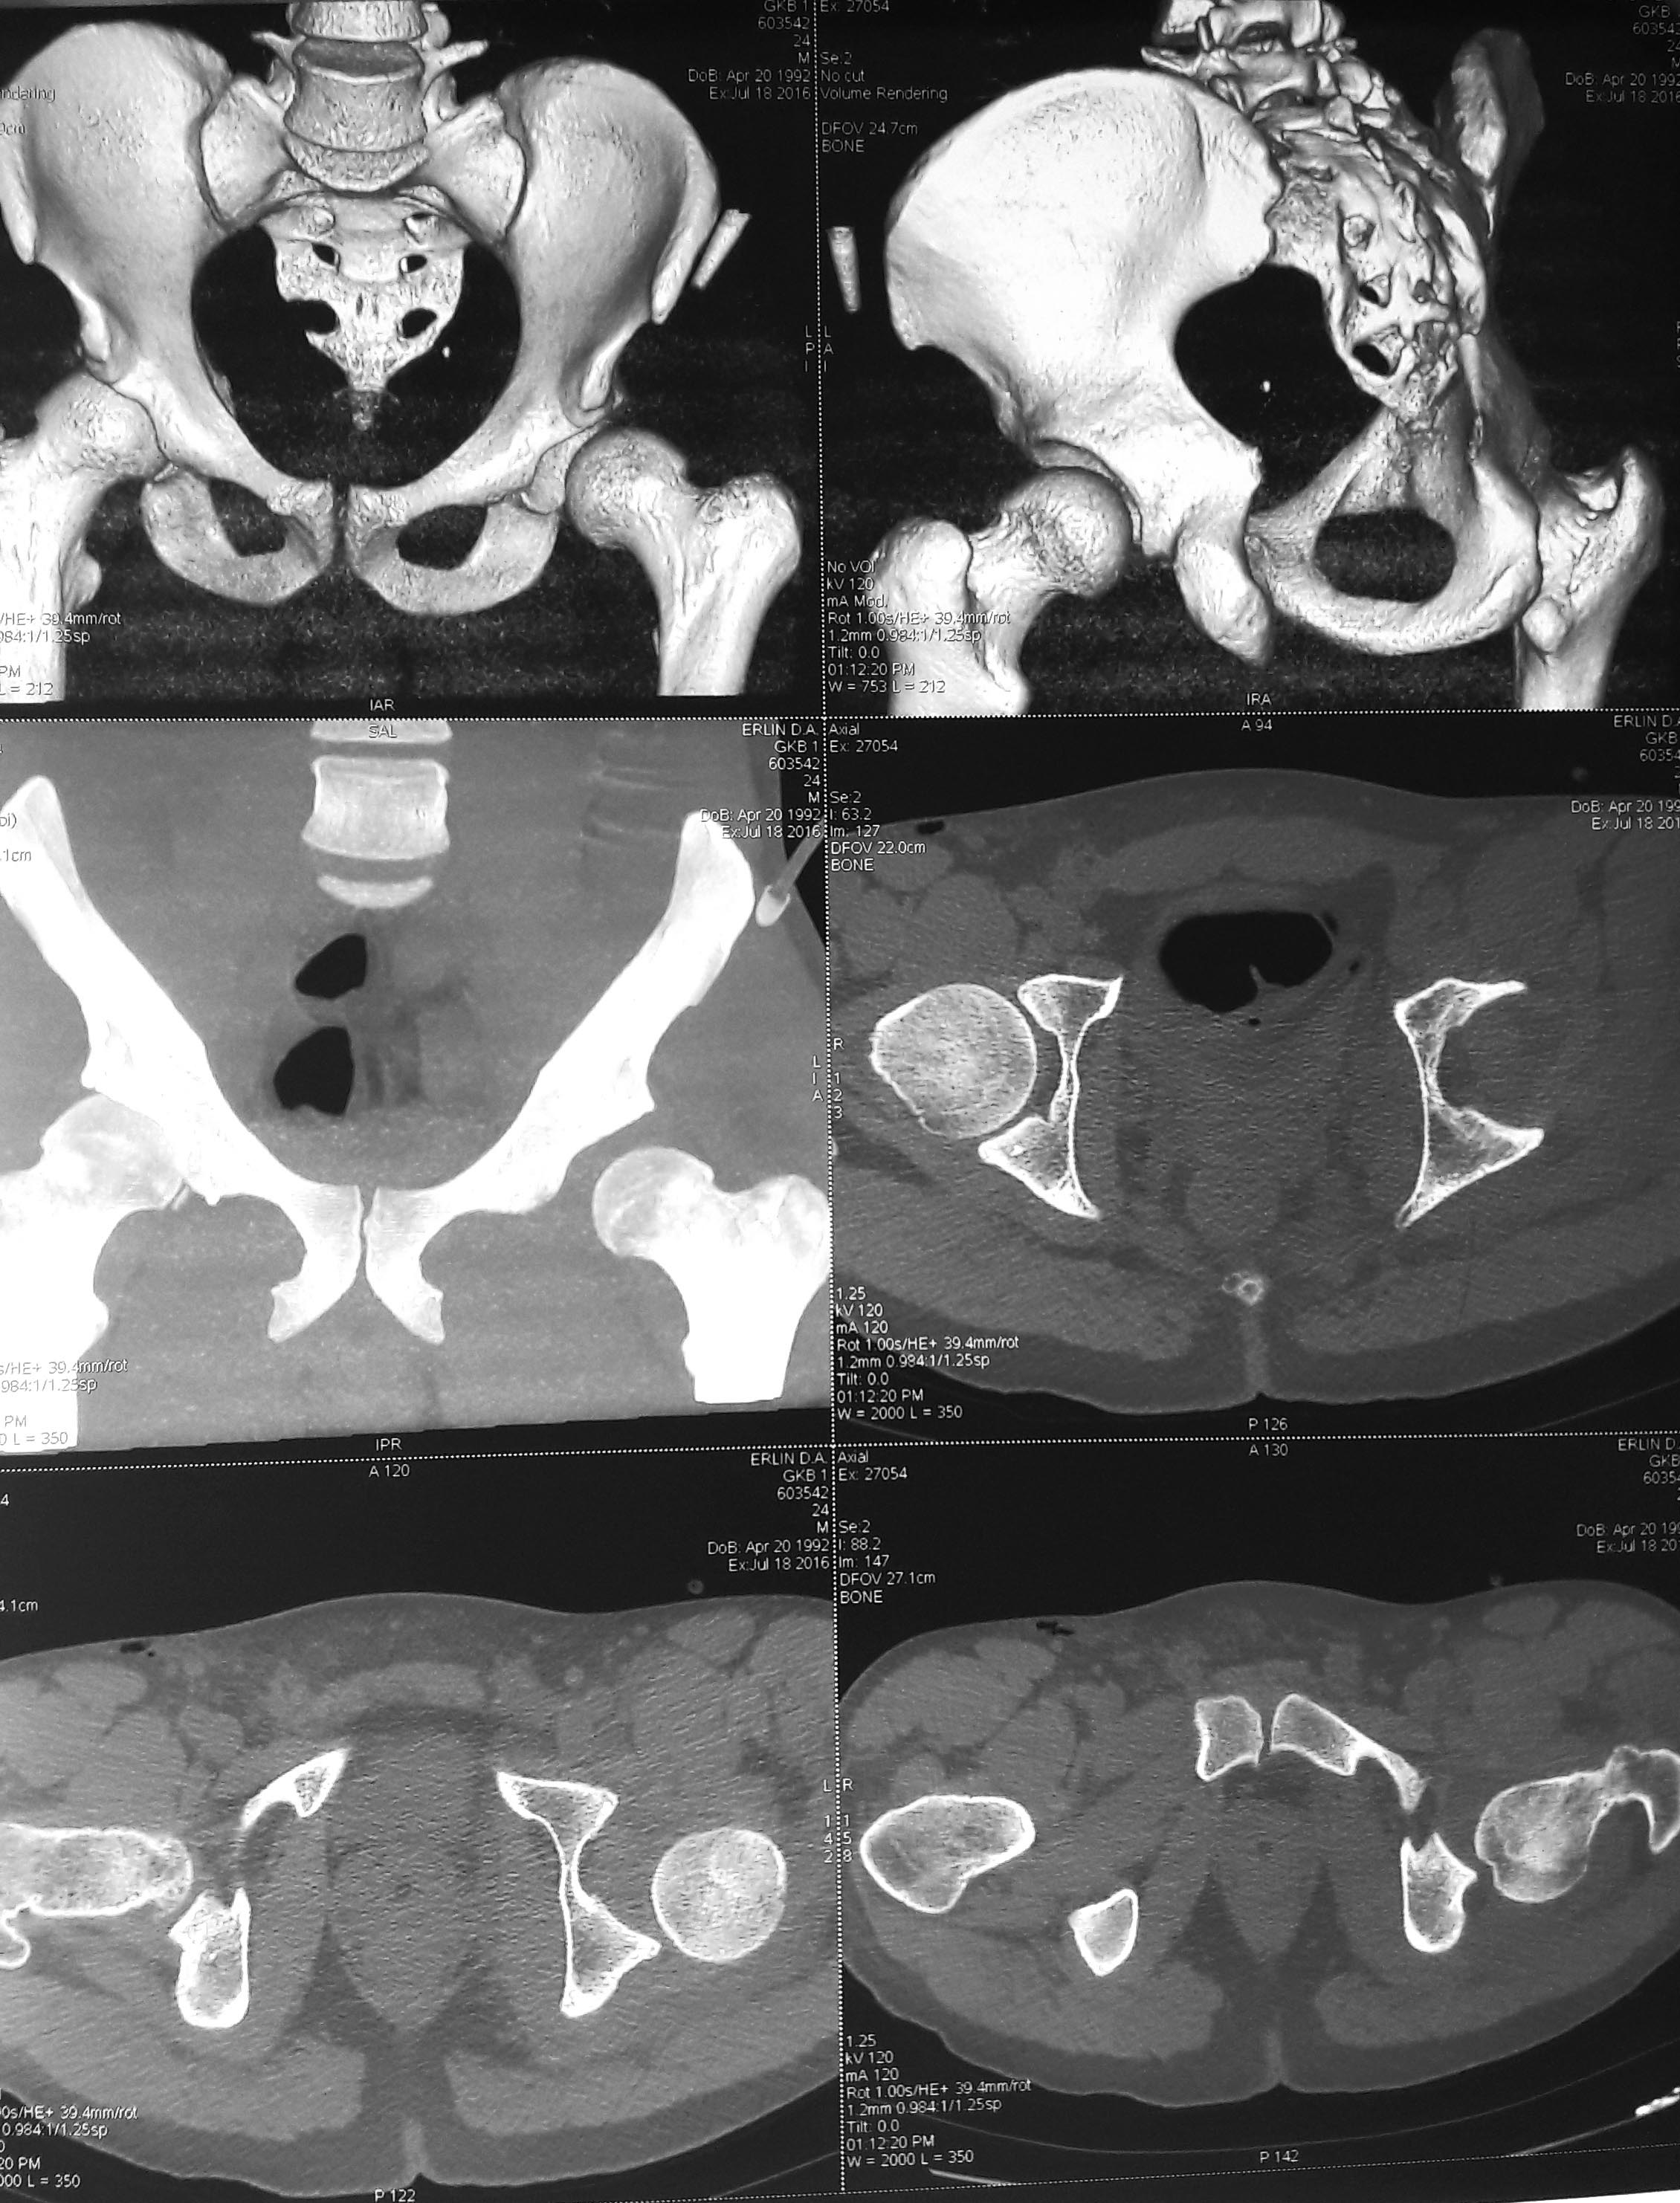

Уважаемые коллеги!Пациент, 24 года, автодорожная травма, неделю назад. Закрытый вывих бедра слева, рваная рана промежности, гематома мошонки. При поступлении вправление вывиха, пхо раны. Деротационная шина.На следующий день-на контроле-повторный вывих повторное вправление, скелетное вытяжение. Rn-граммы и КТ высылаю. Это недовправленный вывих, интерпозиция м/тканей или парез мышц,участвующих в позиционировании головки? Пока на ваытяжении. Что дальше с ним делать? Спасибо.

Случай не самый обычный. Выраженная дисплазия вертлужной впадины. Покрытие головки недостаточное. Того, к чему мы привыкли, когда вправленную головку так просто снова не вывихнешь, здесь не будет. Она и до травмы во многом держалась за счет мягких тканей, которые теперь повреждены. Может и парез каких-то мышц есть, по снимкам не скажешь. Что делать дальше? Наверное снять вытяжение. Какова его цель в данном случае? Если есть ЭОП можно было бы посмотреть, что происходит при вправлении. Действительно ли головка вправляется и в каком положении ноги удерживается в суставе? Если удерживается, попробовать зафиксировать ногу в этом положении (АВФ?). А если не вправляется, думать об открытом вправлении с последующей фиксацией. И что за рана в промежности? Насколько обширная, как заживает, позволяет ли оперировать? И еще, нет ли у пациента разрыва крестцово-подвздошного сочленения?

Рана 10 см., заживает. Швы планируем в ближайшие дни снять. Разрыва кпс нет, посмотрели на КТ повторно, все симметрично во всех проекциях.

Простите а где Вы здесь увидели ВЫРАЖЕННУЮ дисплазию. Конечно философски можно любой сустав назвать диспластичным, но ... Ну незначительная может и присутствует не более, я бы назвал это вариантом. Прост за живое задело, раздражает когда слишком часто и необоснованно коллегами выставляется дисплазия тазобедренных суставов. А случай конечно неординарный. Думаю здесь имеет место полный отрыв губы с возможным односторонним разрывом мышц. Прогноз неблагоприятный суставу несомненно не жить. Но в среднесрочной перспективе здесь достаточно простое протезирование, а сейчас конечно открывать и артропластика.

Интерпозиция, требуется устранить открыто. С Ув. АВБ

Капсула, возможно сорванный хрящ с головки, вместе со связкой головки. Поэтому, не стоит играться с дополнительными закрытыми вправлениями.